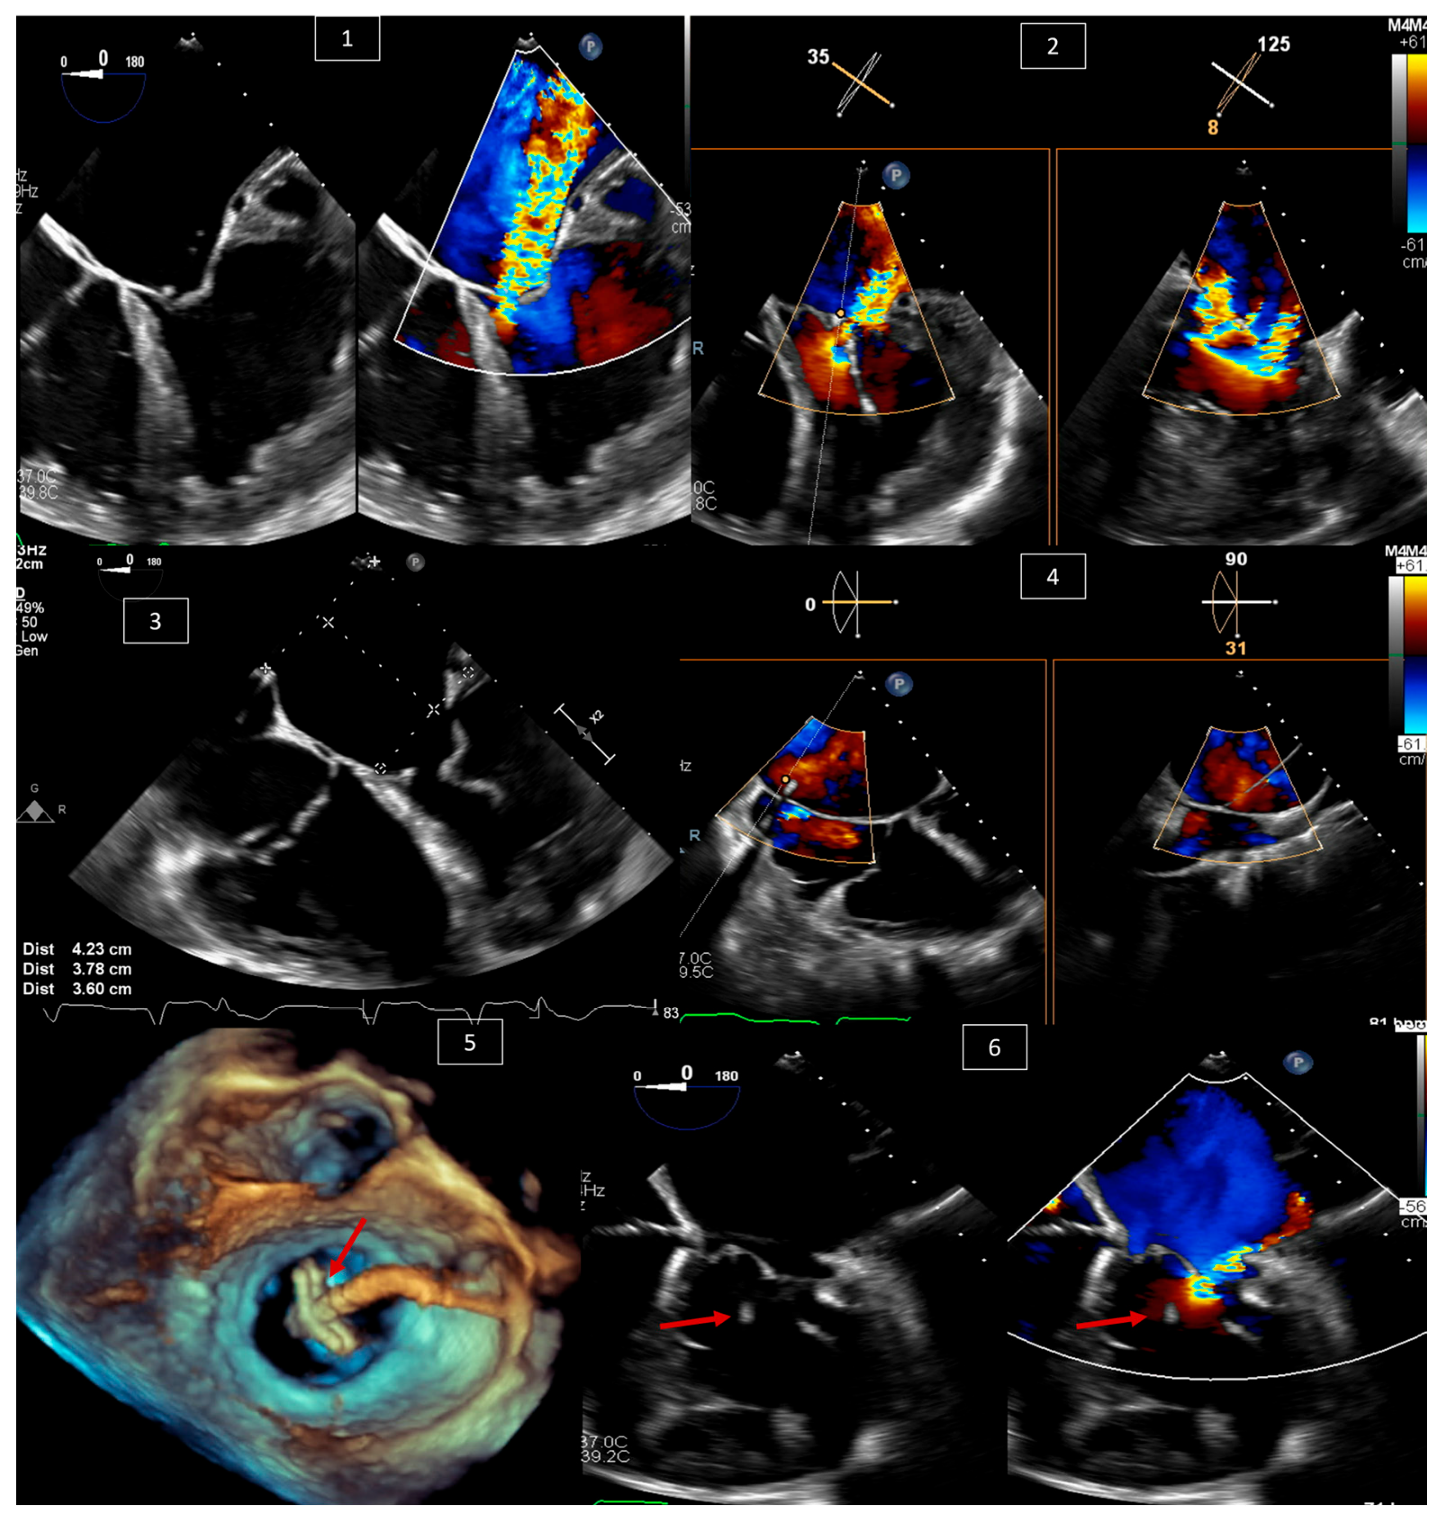

4. Transcatheter Edge-to-Edge Repair (TEER) of Systemic AV Valve